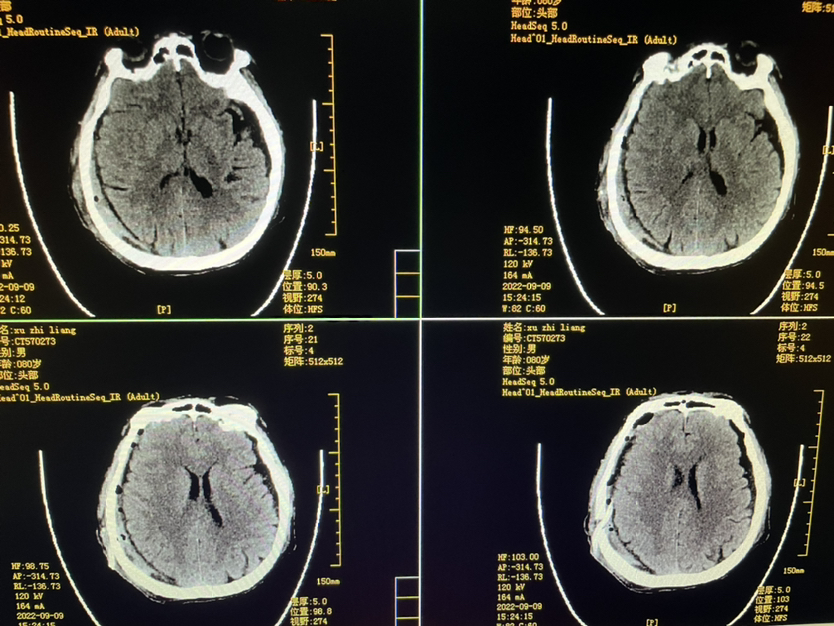

明确外伤史二月,80y,